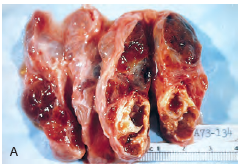

What is this?

Multinodular goiter lacking a capsule. Notice how the thyroid tissue is being squished